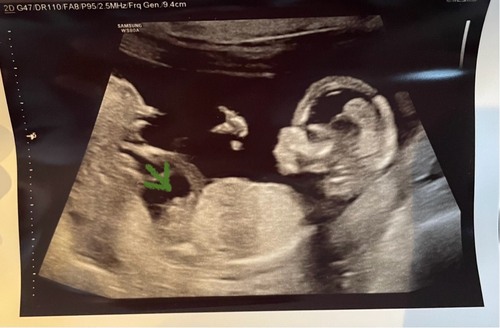

Kan echt beide zijn 🤭 voor de 15 weken lijkt het vaak nog heel erg op elkaar. Veel plezier morgen!

Aan de vorm van het hoofdje zou ik zeggen een meisje.. maar het groene pijltje kan ik nog niet veel uit opmaken 😅

Ik zou hier gokken op een meisje, maar het kunnen net zo goed de balletjes zijn ☺️

Ik denk een jongetje. Ik gok dat het morgen nog wat aan de vroege kant is maar ik ben benieuwd, laat je het weten morgen?

Ik zou denken een meisje gezien de 'stand'... Veel plezier vandaag met de echo!